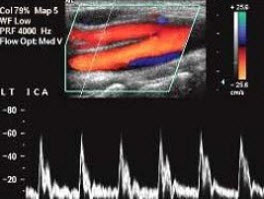

175、单项选择题

如图所示,该频谱为下列那支血管的频谱特点()

A.颈外动脉

B.颈内动脉

C.颈总动脉

D.颈内静脉

E.椎动脉

176、单项选择题 正常肝静脉频谱特点()